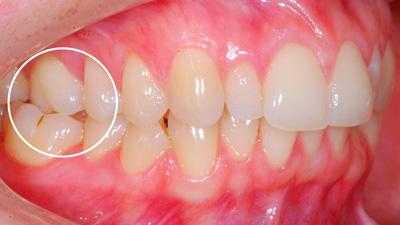

Определяющими внутриротовыми признаками дистального прикуса служат выдвижение вперед верхних фронтальных зубов; несмыкание верхних и нижних резцов с наличием между ними сагиттальной щели; нарушение взаимного расположения боковых зубов в переднезаднем направлении. В чистом виде дистальный прикус встречается редко; гораздо чаще он сочетается с аномалиями положения зубов, диастемой, тремами, глубоким, открытым или перекрестным прикусом, готическим нёбом.

Внутриротовые признаки

В полости рта дистальный прикус определяется по выступающим вперед верхним фронтальным зубам. В норме, при ортогнатическом прикусе, верхние резцы перекрывают нижние примерно на 1/3. При дистальной патологии между верхними и нижними резцами образуется расстояние — «саггитальная щель».

- I подкласс — верхние резцы направлены вперед, иногда немного вверх. Для этого вида дистальной окклюзии характерная саггитальная щель.